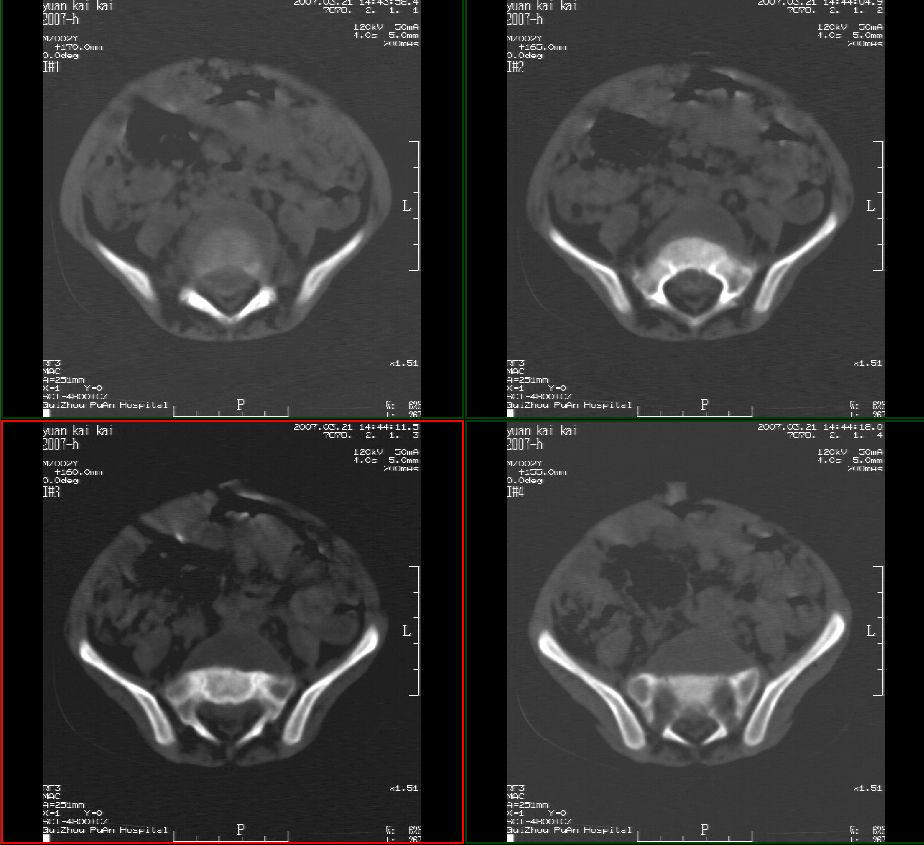

男性,2岁半,髋部疼痛10月,伴跛行,请大家会诊!

骶骨无明显吸收破坏征像,骶前见囊性占位,考虑:骶前脊膜膨出。

骶前脊膜膨出(anterior sacral meningocele):位于腰骶交界处有先天椎体缺失,膨出的硬脊膜和蛛网膜通过骶骨腹侧缺损,向骶前膨出,称骶前脊膜膨出。囊内一般无神经组织,有时神经根也会疝入到囊腔内,产生临床症状。而此患者椎体未见椎体缺损。